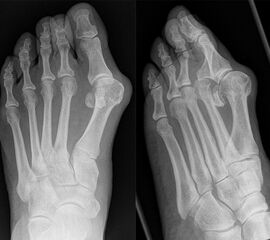

An erster Stelle der bildgebenden Diagnostik steht die konventionelle Röntgendiagnostik. Der betroffene Fuß wird dabei unter Belastung in 3 Ebenen dargestellt. Beurteilt werden der Intermetatarsale-I-Winkel (IM-Winkel), der Hallux valgus Winkel (HV-Winkel), die Lage der Sesambeine, der Arthrosegrad im MTP I Gelenk und ein mögliches plantares Klaffen „gapping“ im Tarsometatarsale-I Gelenk als Hinweis auf eine Gelenkinstabilität. Neben der reinen Beurteilung des Hallux valgus sollten immer auch die Kleinzehen beurteilt werden.

Sowohl für die Scarf-Osteotomie 4232425, als auch für die Ludloff-Osteotomie 52627 sind in der Literatur gute Resultate dokumentiert. Choi et al. 28 berichteten in einer prospektiven Fallkontrollstudie über eine sehr gute Korrektur des Hallux valgus Winkels von 29° auf 10,6°, des Intermetatarsalwinkels von 13,6° auf 5,6° bei guter Rezentrierung der Sesambeine. Die Gesamtkomplikationsrate lag bei 15%. Eine Hallux varus Fehlstellung entwickelte sich in 4%, eine progrediente Arthrose führte in 4% zur Notwendigkeit einer Arthrodese.